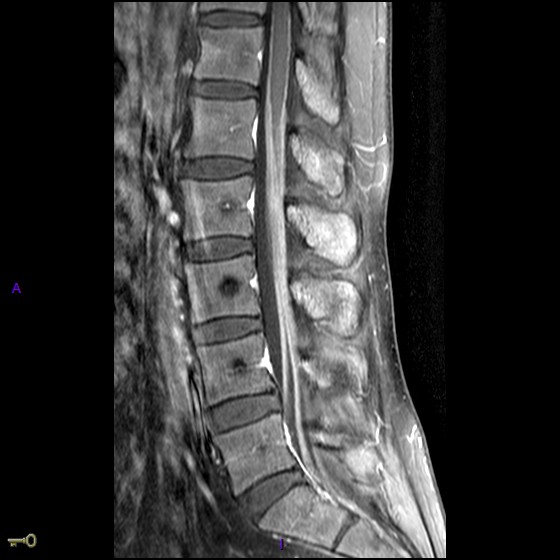

Prise de contraste leptoméningée étendue intéressant le cône médullaire et l’ensemble des racines de la queue-de-cheval.